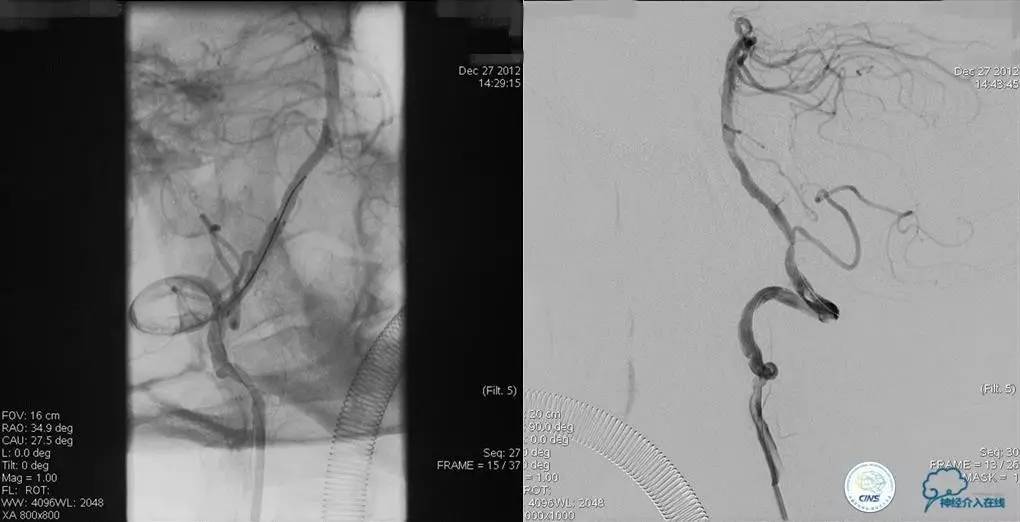

术前DSA

▼2013-12-27